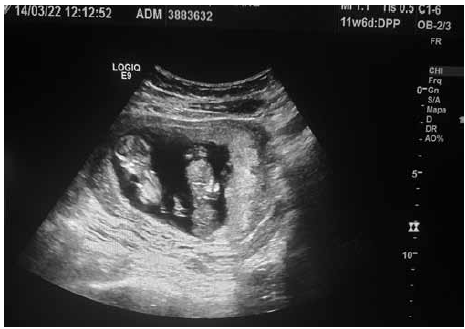

Figura 1

Com base nas figuras 1 e 2, o melhor manejo pré-natal para a paciente é:

Paciente com IG de 12 semanas pela DUM veio à medicina fetal para realização de seu primeiro ultrassom obstétrico. Identificadas as figuras 1 e 2 (em ângulos e posições diferentes), conforme ilustrado.

Com base nas imagens em conjunto, assinale o diagnóstico correto é: